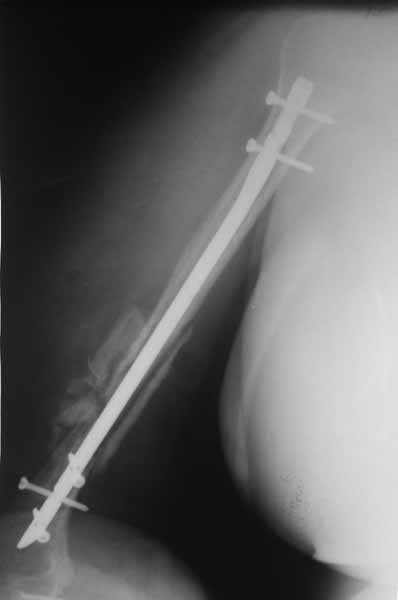

[Ortho] Застарелый вывих головки плечевой кости

Имя     : IMG_0161.jpg